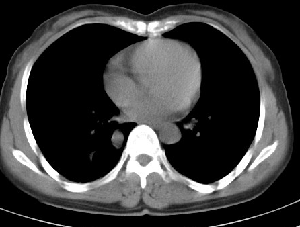

下叶后基底段近膈面见一椭圆形密度均匀增高的阴影,边界较清,其长轴指向内后方,考虑肺隔离症,建议增强扫描了解与主a联系!

右下肺隔离症有可能,另外可能是炎性假瘤

右下肺隔离症考虑,不除外炎性假瘤,建议增强。

右下肺隔离症可能性大,不除外炎性假瘤、神经原性肿瘤

考虑:右下肺隔离症可能性大,不除外炎性假瘤,谨慎点+神经原性肿瘤,支持20楼